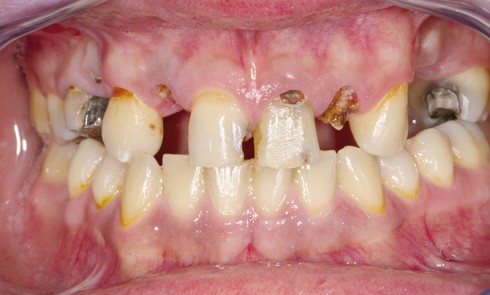

Article réservé à nos abonnés Protocole de mise en charge en 36 heures chez l’édenté total

De nos jours il est presque inconcevable de proposer un traitement implantaire au patient en voie d’édentement au maxillaire sans...